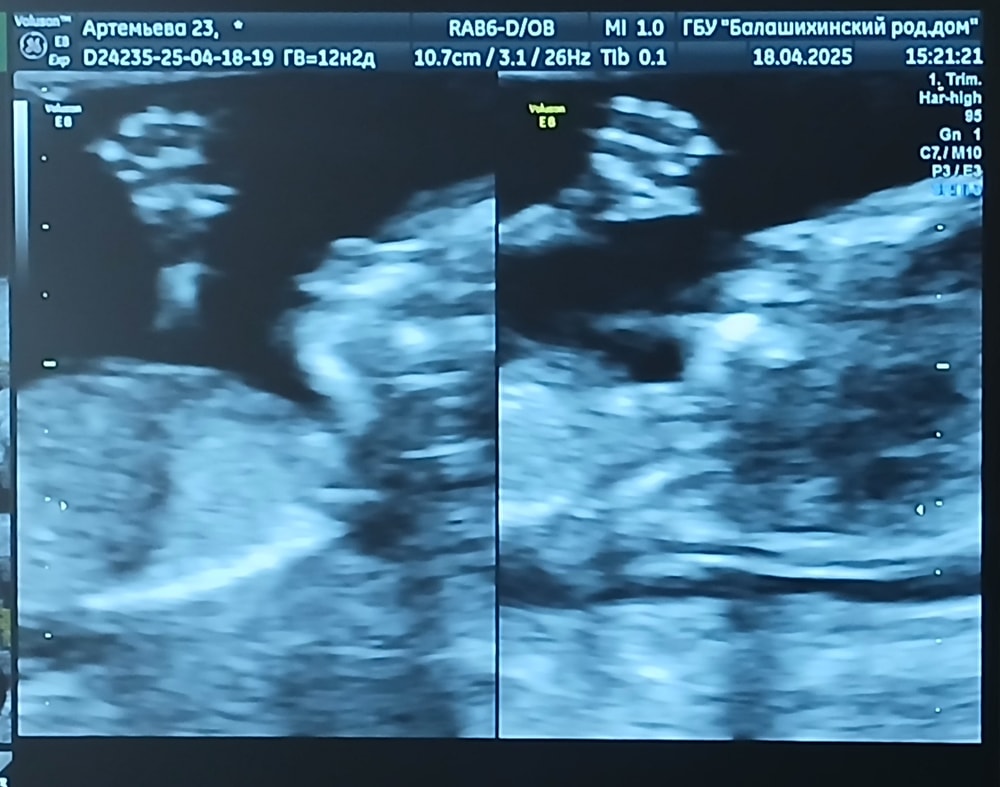

1 скрининг. 12 недель 🤰

Сегодня ровно 12 недель. По УЗИ все хорошо 🙏🏼 Жду результат анализа крови.

КТР 60

БПР 18

Длина бедра 7.7

ОГ 68

ОЖ 57

ТВП 1.6

Носовая кость визуализируется

ЧСС 153